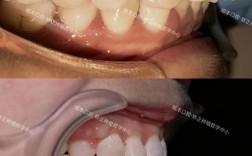

- 牙釉质磨损与脱矿:固定矫正器(如托槽、弓丝)易导致牙齿清洁死角,食物残渣和菌斑堆积,酸性物质腐蚀牙釉质,引发“白斑病”(早期龋齿),数据显示,矫正儿童牙釉质脱矿发生率高达50%以上,若未及时干预,可能发展为龋洞。

传统矫正器的托槽、弓丝末端可能摩擦口腔黏膜(如颊黏膜、舌缘),引发溃疡、糜烂,儿童好动且自控力弱,易误吞或误矫正器部件,造成窒息风险或消化道损伤,隐形矫正器虽边缘光滑,但若贴合度不佳,仍可能压迫牙龈,导致牙龈退缩或炎症。